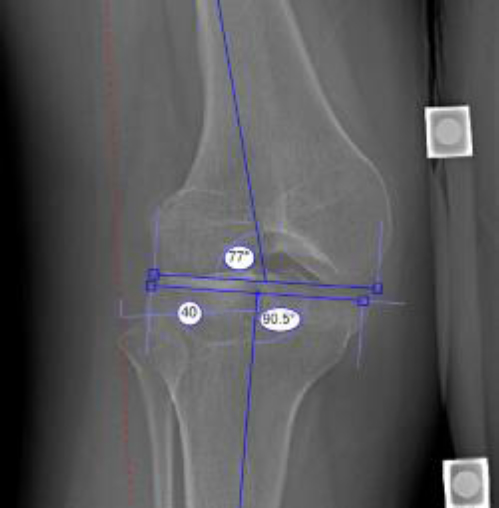

[Electronic Publication Date: March 04, 2026]Cedrick Sangwa Milindi, Yve Yuma, Christian Tshisuz, Deance Mbaya, Mireille Kakinga, Dominique Muhindo, Salamata Dieng, Elie Sadoki, Yve Kayembe and Adelin Muganza